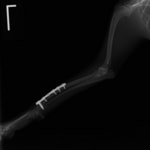

症例:交通事故による椎体脱臼

柴犬:9歳、避妊雌

交通事故直後、胸腰部に激しい疼痛、両後肢に完全麻痺を認め、シェフシェリントン徴候を呈していました。レントゲン検査において、第11-12胸椎間の脱臼が認められました。

脊髄の減圧、脊柱管の再構築・安定化を目的に、片側椎弓切除術およびMatrixMANDIBLE Plateによる椎体固定を実施しました。

隣接椎体を架橋するようにプレートを設置しました。

術後レントゲン写真